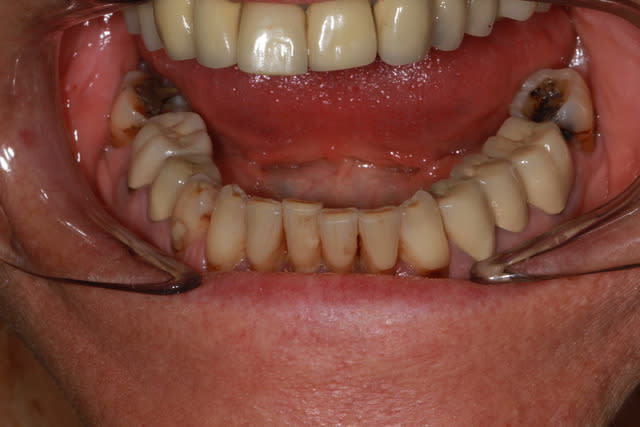

une radio d'implant, pas terrible mais peut être suffisante pour toi Pluton?

Pourquoi des facettes d'usures si importantes sur les 7? et bord libre 11?

Inflammation paro chronique, sites actifs? qu'est ce qui bouge?

26,27,17,24 m'ont l'air foutues, 11 peut-etre aussi. Mobilites?

j'ai mis en rouge toutes les zones très malades, voir suceptibles d’être en fin de vie...